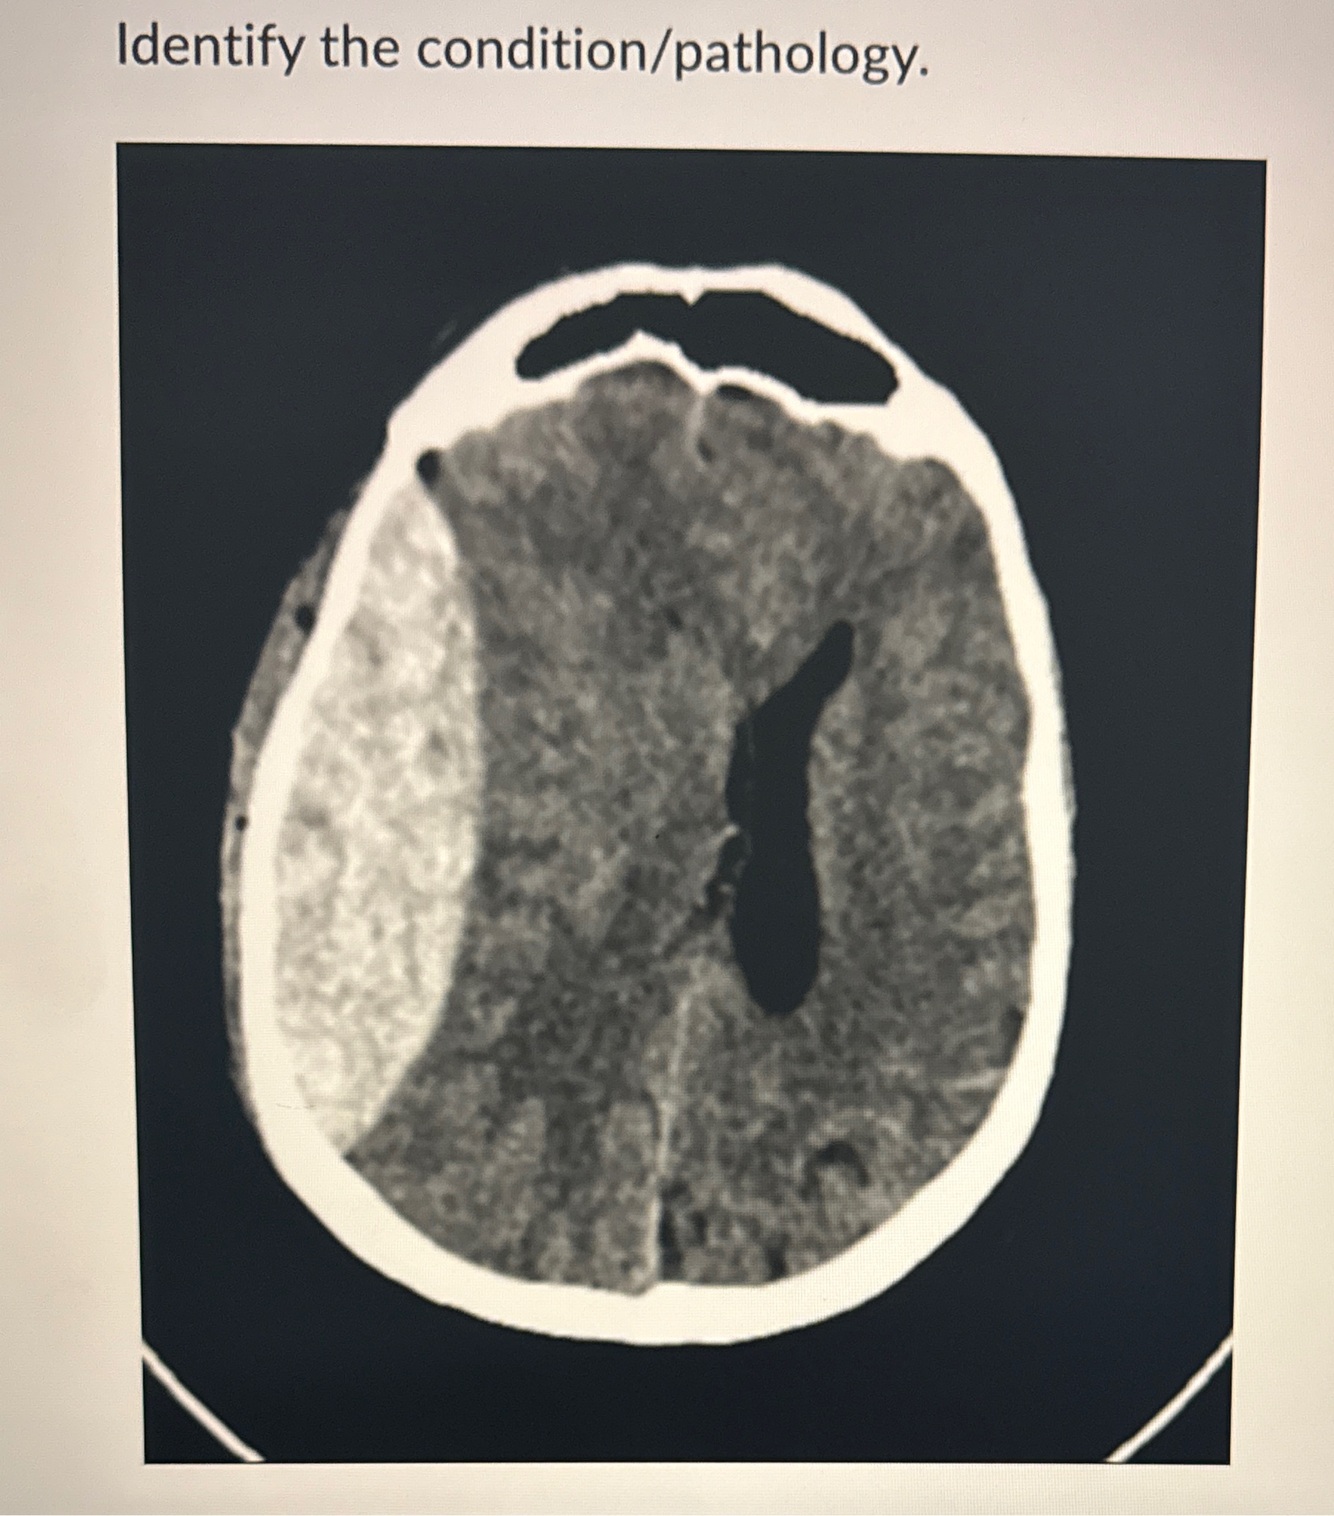

Epidural Hematoma Intracerebral Hemorrhage Subarachnoid Hemorrhage

Subdural Hematoma

Epidural Hematoma